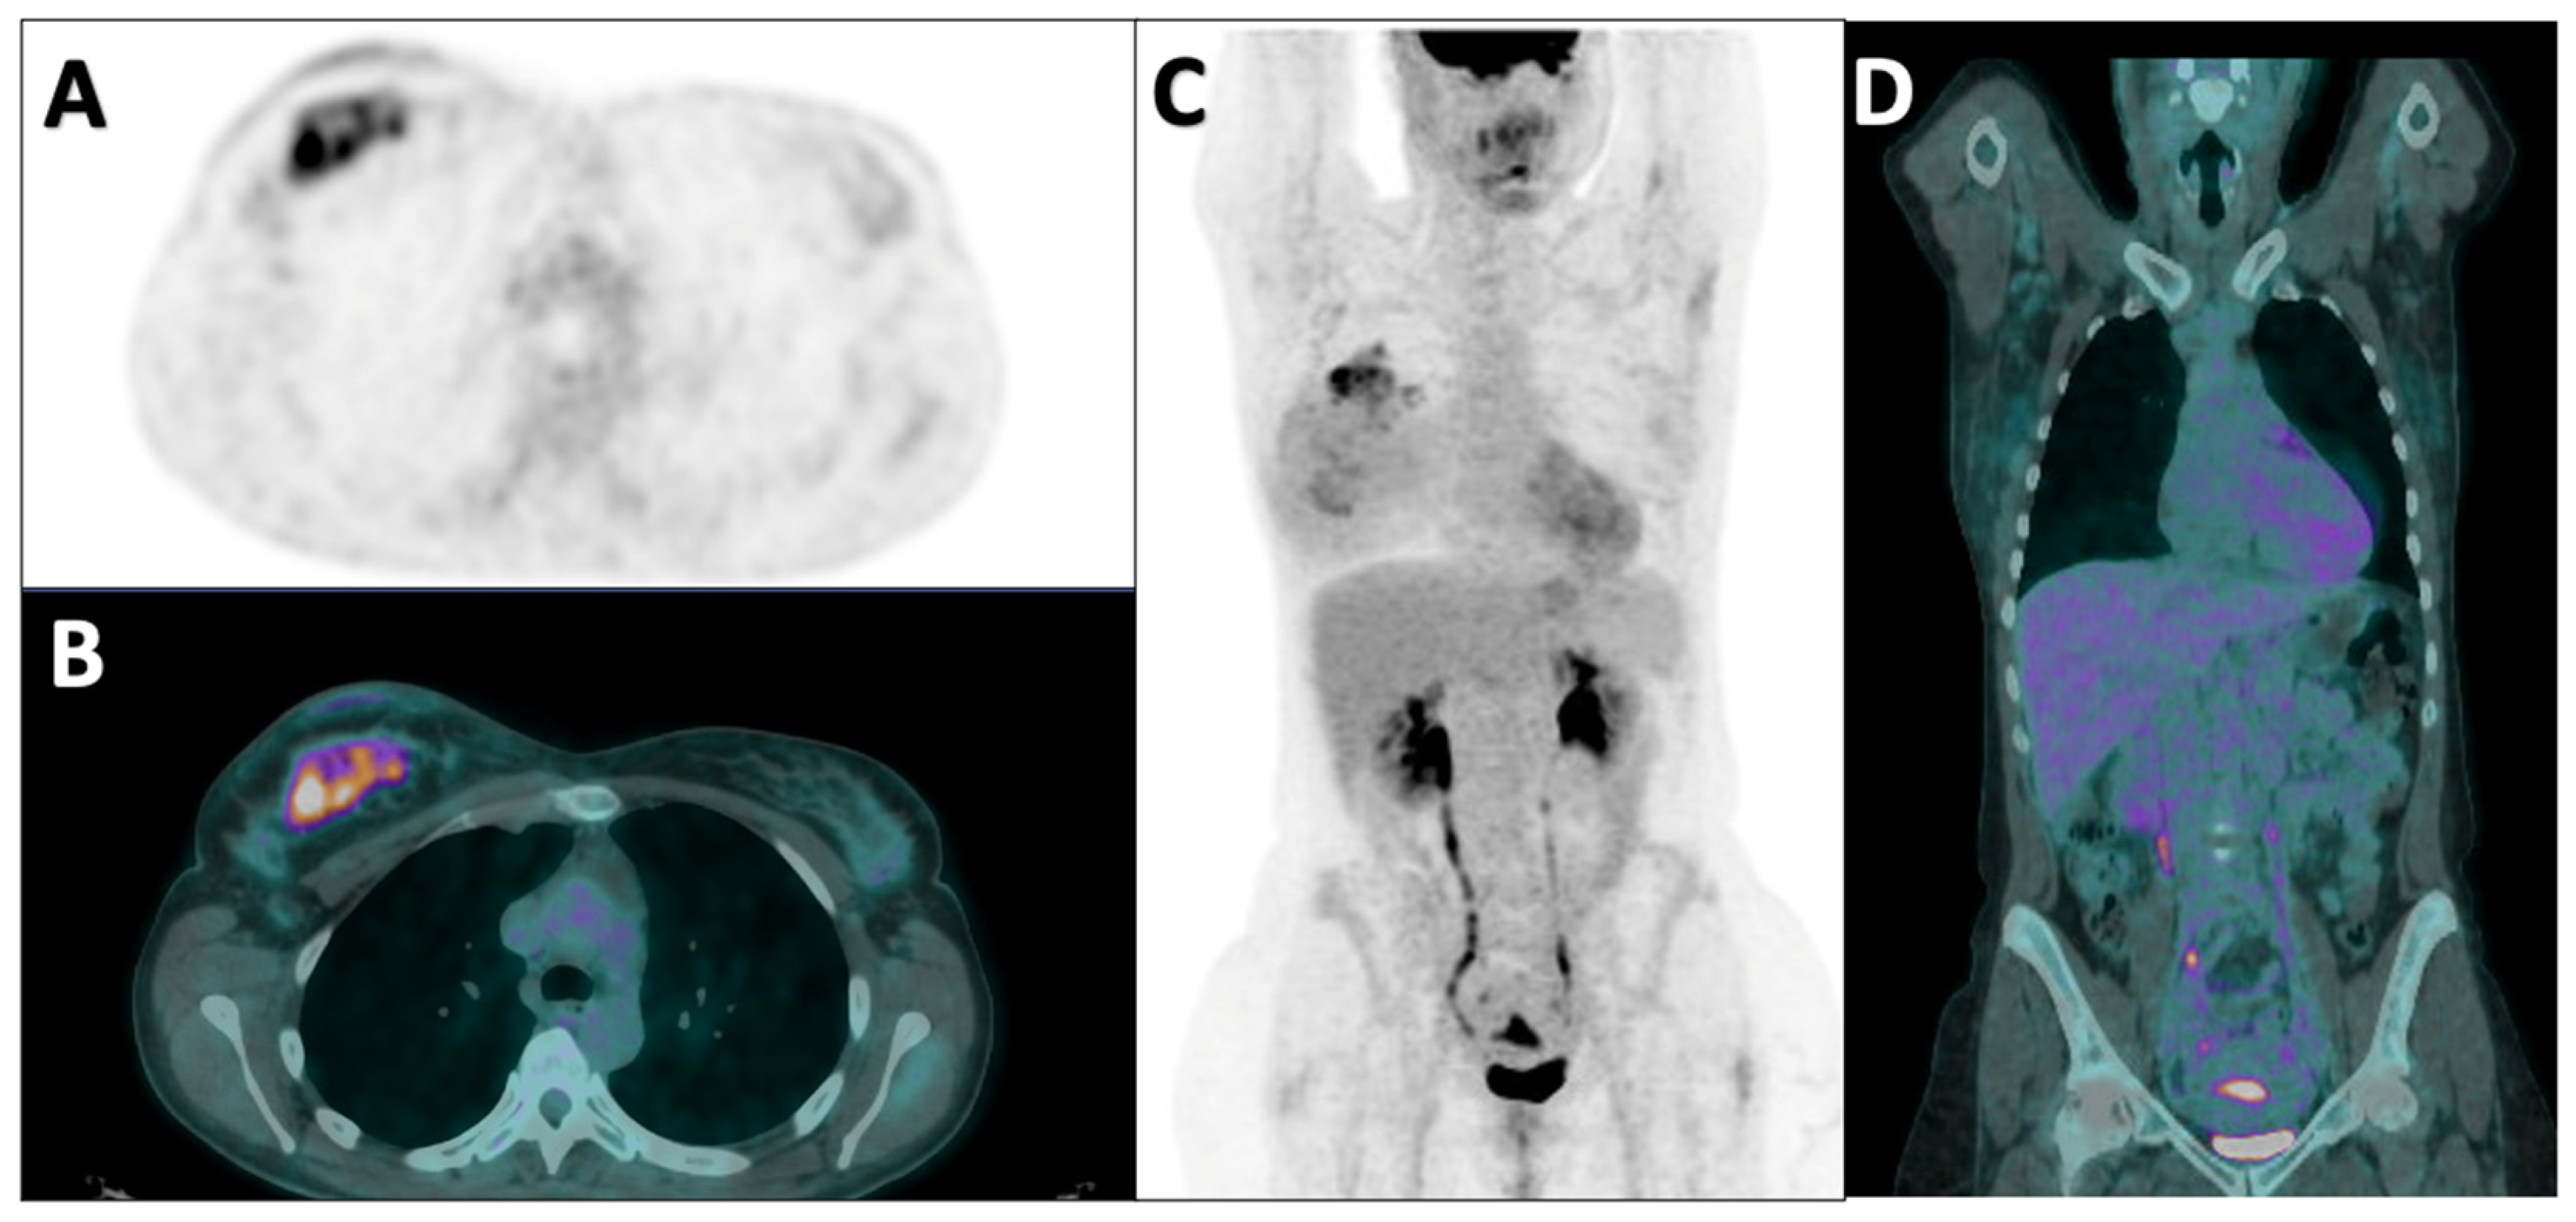

2.2. PET Acquisition and Image Analyses